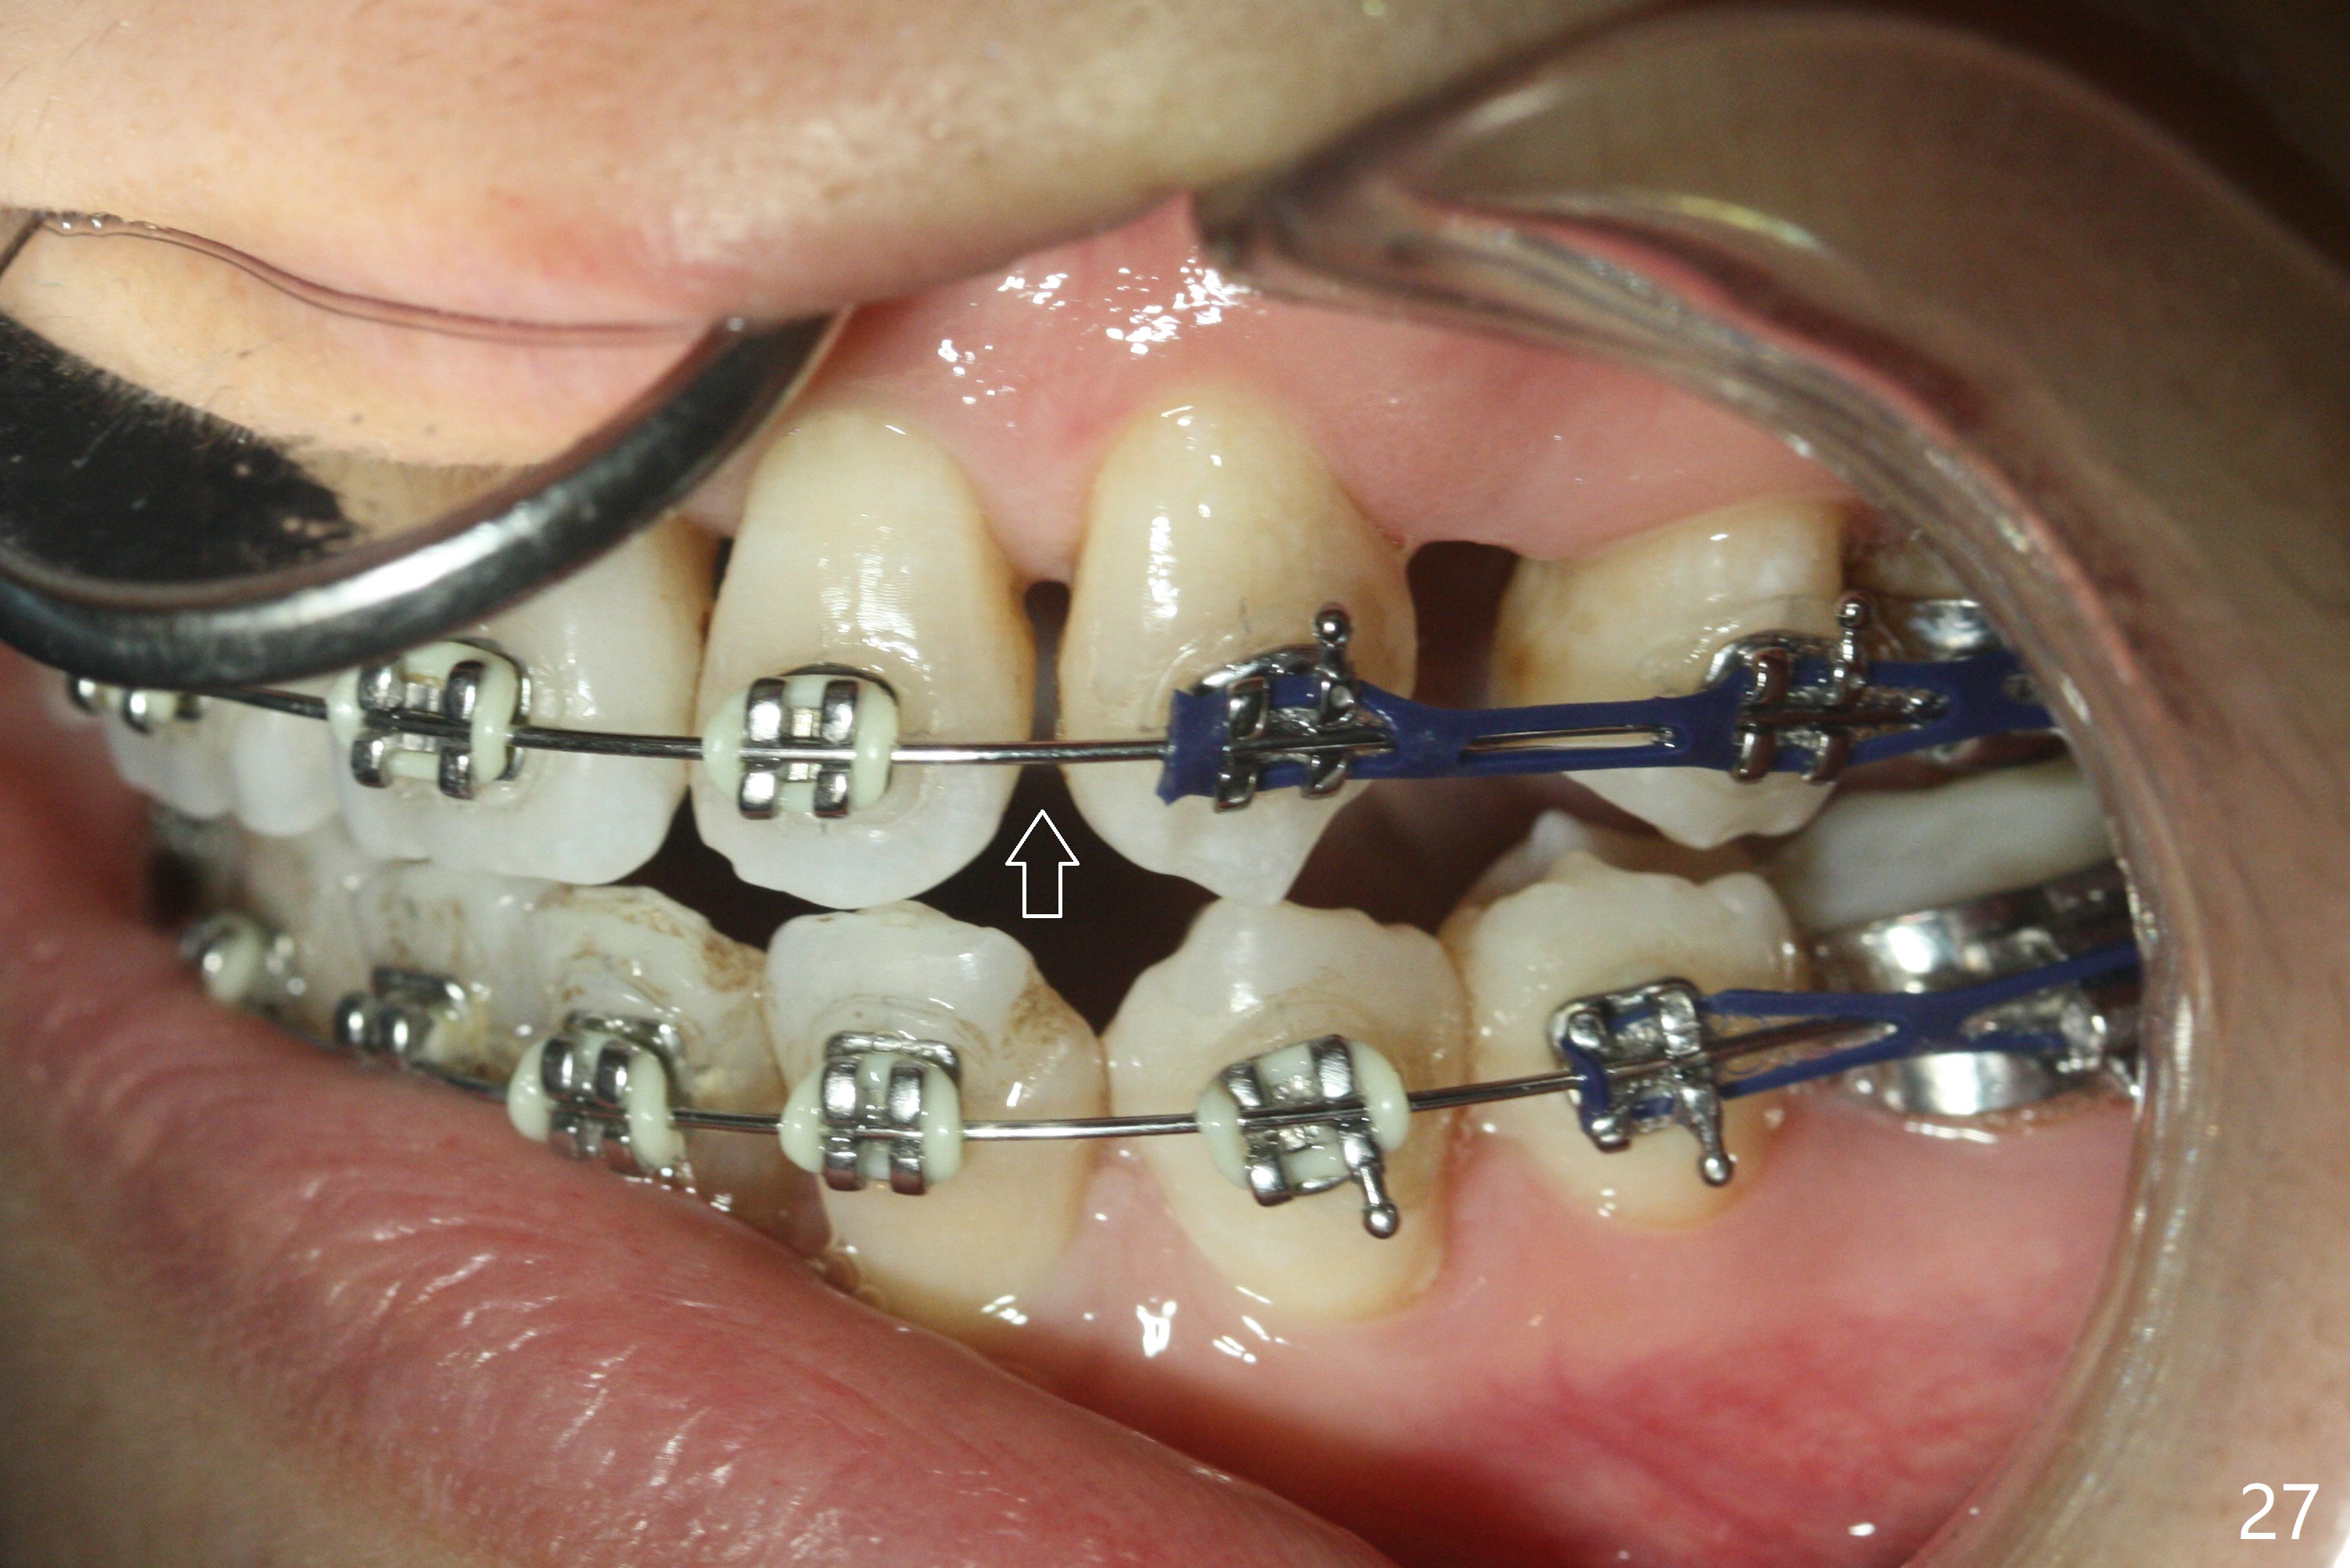

Eight months post banding, UR3 appears to be distalized with de-rotation (Fig.26), while UL3 is slightly over-distalized with mesial space (Fig.27 arrow). LL5 remains rotated (Fig.28). One months later, anterior over bite and over jet seem to be normal. In spite of lack of Class I anterior occlusion, it is decided that the upper posterior teeth should be mesialized. Next visit, wires will be changed to 16x16 with ligature wire between U3-3 and power chains between U3 and 5.